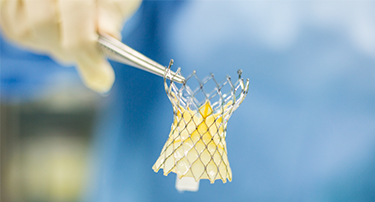

Modern Cardiac Care: The Role of TAVR in Structural Heart Disease Treatment

Nature is just amazing. Look at the amazing things. Just look around, or better yet, look within yourself. Your heart, for example, is a true marvel, working tirelessly, 24/7, never taking even a nap.

Innovative Heart Valve Solutions That Avoid Open-Heart Surgery

For decades, open-heart surgery was the sole method for repairing or replacing a defective heart valve. Although effective, the old method is marked by giant incisions, extended recovery periods, and jeopardy to elderly or high-risk patients.

TAVI Vs. Open-Heart Surgery: Which Is The Right Choice For You?

For heart valve replacement, patients usually have two primary choices: Transcatheter Aortic Valve Implantation (TAVI) and open-heart surgery. Both involve replacing a faulty aortic valve, but they are very different in approach, recovery period, and applicability to various patient populations. Knowing the main differences, advantages, disadvantages, and success rates can assist you in making an informed choice.

Who Is The Ideal Candidate For TAVI? Understanding Eligibility & Benefits

Transcatheter Aortic Valve Implantation (TAVI) has revolutionized the treatment of severe aortic stenosis, especially for patients who are high-risk candidates for traditional open-heart surgery. This minimally invasive procedure offers a lifeline to many, but determining who stands to benefit the most is crucial.